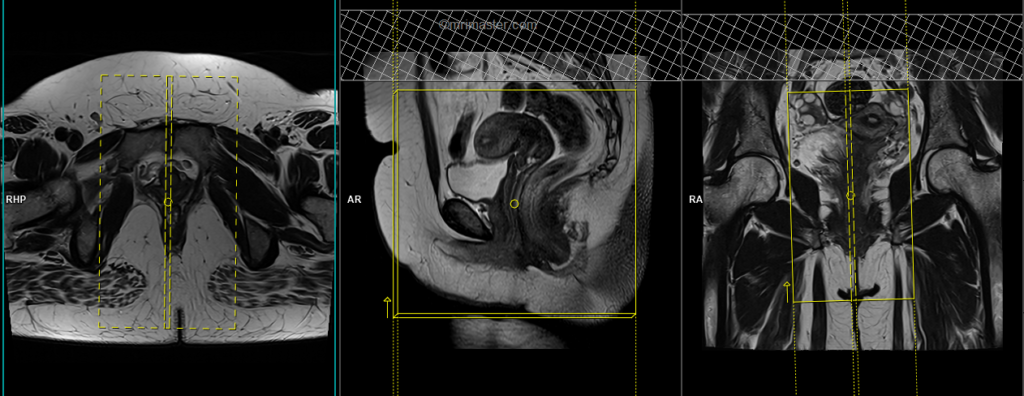

T2 tse sagittal 3mm

Plan the sagittal slices on the coronal plane; angle the planning block parallel to the vagina (i.e., parallel to the interpubic fibrocartilage). Check the planning block in the other two planes. An appropriate angle must be given in the axial plane (parallel to the interpubic fibrocartilage and the anal canal). Slices must be sufficient to cover the pelvis from the right acetabulum to the left acetabulum.

Parameters

TR 3000-4000 | TE 100-120 | SLICE 3 MM | FLIP 130-150 | PHASE H>F | MATRIX 320X320 | FOV 250-300 | GAP 10% | NEX(AVRAGE) 2 |